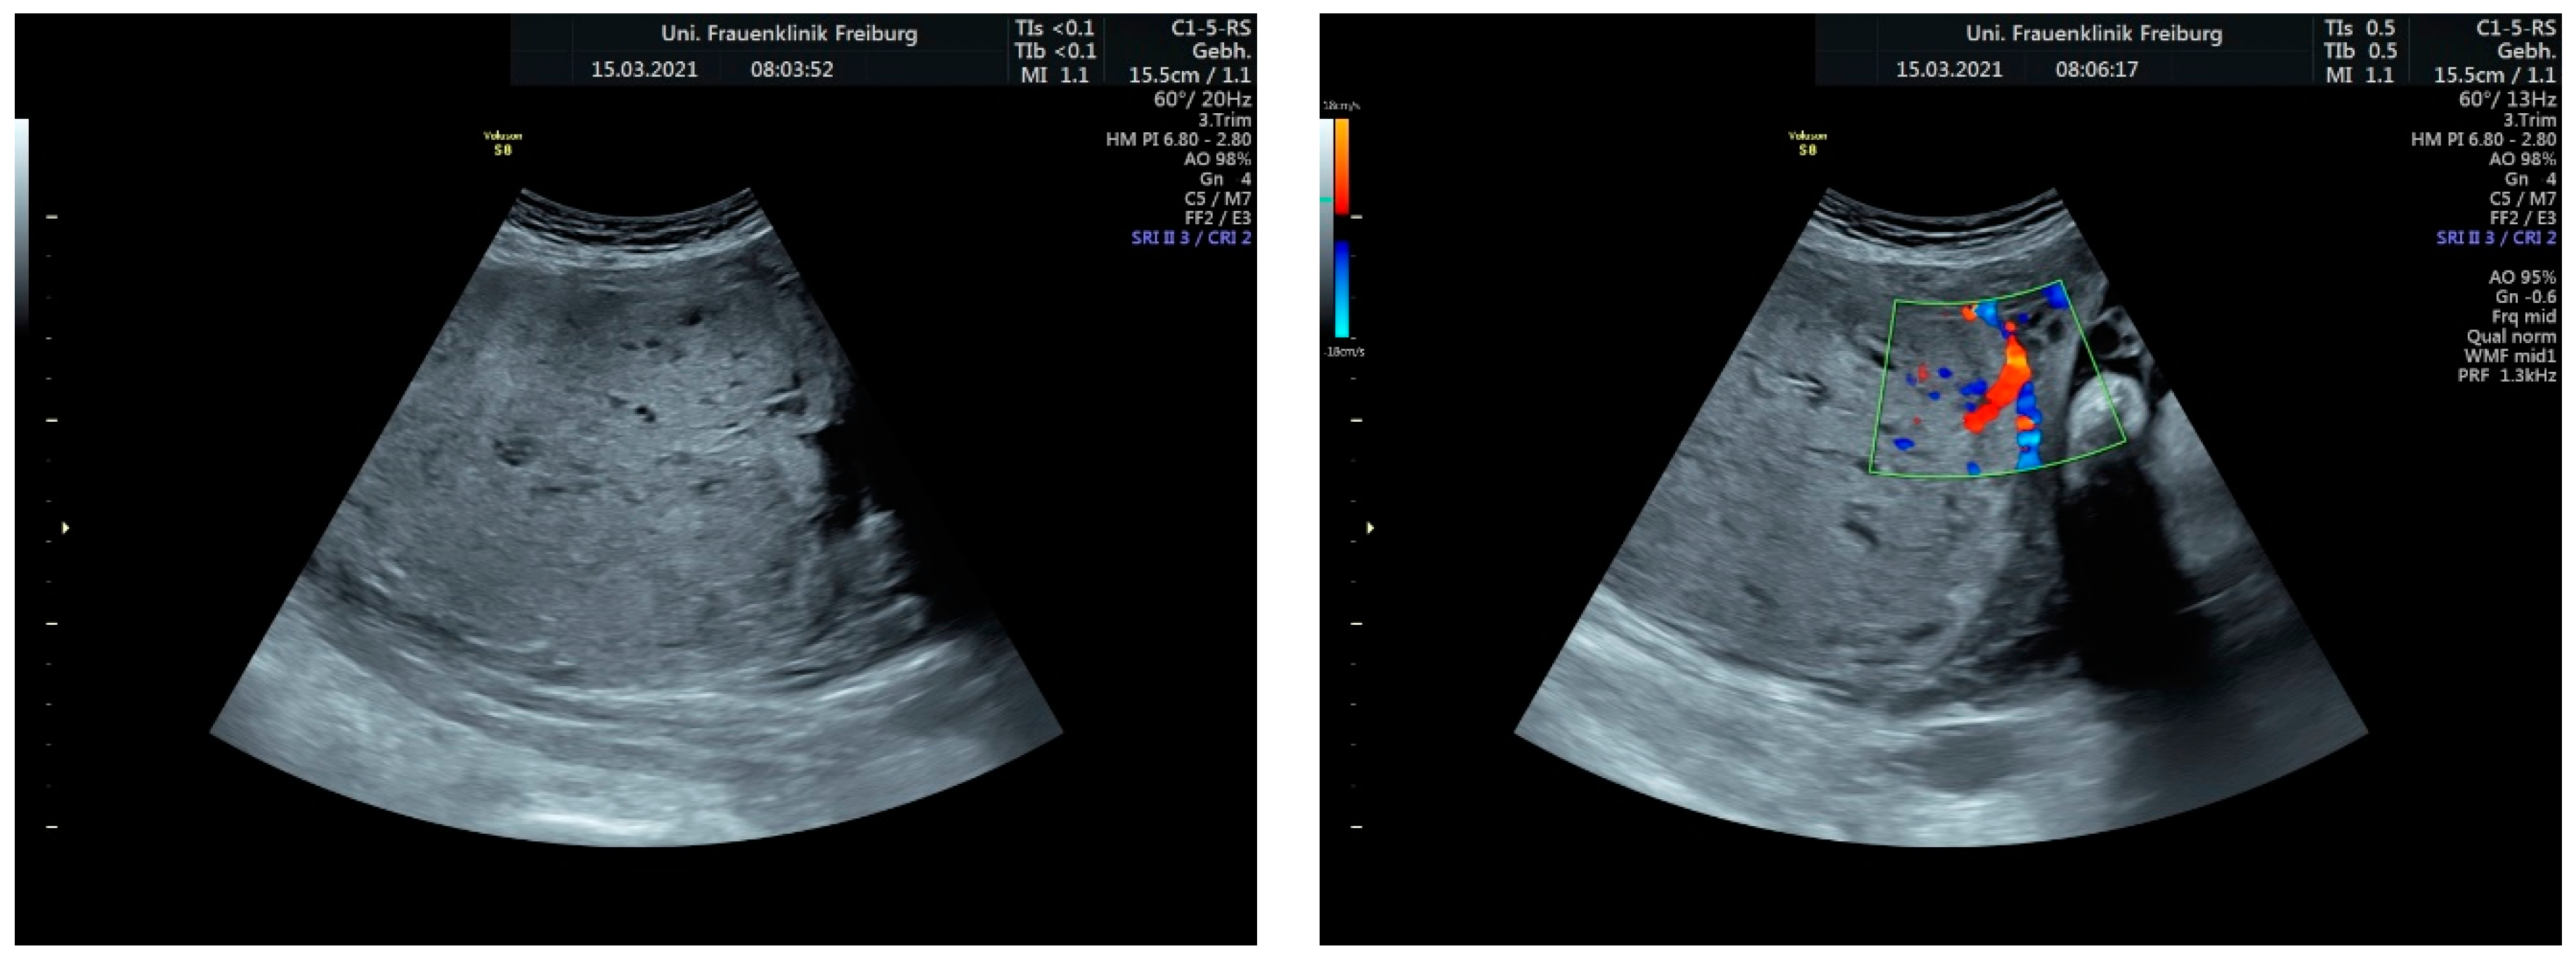

Sonographic findings (Figure 9):

Figure 9.

Irregular, large lacunae within the placenta, Hypervascularity, Turbulent flow inside the lacunae Diameter gaps.